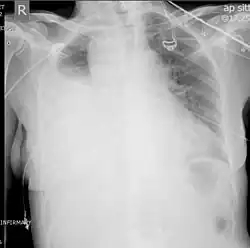

Hemothoraces are most commonly detected using a chest X-ray, although ultrasound is sometimes used in an emergency setting.[22] It can be suspected in any person with any form of chest trauma.[6] However, plain X-rays may miss smaller hemothoraces while other imaging modalities such as computed tomography (CT), or magnetic resonance imaging may be more sensitive.[22] In cases where the nature of an effusion is in doubt, a sample of fluid can be aspirated and analysed in a procedure called thoracentesis.[8] Physical examination is used initially. Auscultation has been reported to have an accuracy of nearly 100% in diagnosing hemopneumothorax.[3]

A chest X-ray is the most common technique used to diagnosis a hemothorax.[23] X-rays should ideally be taken in an upright position (an erect chest X-ray), but may be performed with the person lying on their back (supine) if an erect chest X-ray is not feasible. On an erect chest X-ray, a hemothorax is suggested by blunting of the costophrenic angle or partial or complete opacification of the affected half of the thorax. On a supine film the blood tends to layer in the pleural space, but can be appreciated as a haziness of one half of the thorax relative to the other.[5] A small hemothorax may be missed on a chest X-ray as several hundred milliliters of blood can be hidden by the diaphragm and abdominal viscera on an erect film. Supine X-rays are even less sensitive and as much as one liter of blood can be missed on a supine film.[24]

Ultrasonography may be used to detect hemothorax and other pleural effusions. This technique is of particular use in the critical care and trauma settings as it provides rapid, reliable results at the bedside.[23] Ultrasound is more sensitive than chest x-ray in detecting hemothorax.[25] Ultrasound can cause issues in people who are morbidly obese or have subcutaneous emphysema. When CT is unavailable in the current setting or the person cannot be moved to the scan, ultrasound is used.[3]

Computed tomography (CT or CAT) scans may be useful for diagnosing retained hemothorax as this form of imaging can detect much smaller amounts of fluid than a plain chest X-ray. However, CT is less used as a primary means of diagnosis within the trauma setting, as these scans require a critically ill person to be transported to a scanner, are slower, and require the subject to remain supine.[23][26]

Magnetic resonance imaging (MRI) can be used to differentiate between a hemothorax and other forms of pleural effusion, and can suggest how long the hemothorax has been present for. Fresh blood can be seen as a fluid with low T1 but high T2 signals, while blood that has been present for more than a few hours displays both low T1 and T2 signals.[27] MRI is used infrequently in the trauma setting due to the prolonged time required to perform an MRI, and the deterioration in image quality that occurs with motion.[22]